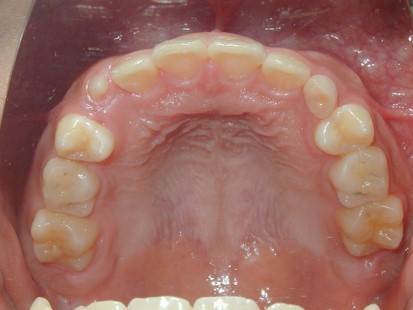

永久歯に交換するためのスペース不足による前歯のガタガタで、取り外しができる拡大床にて上下顎の幅を拡大した後、上顎の前歯をマルチブラケット装置で並べました。治療の期間は1年9か月でした。

初診時